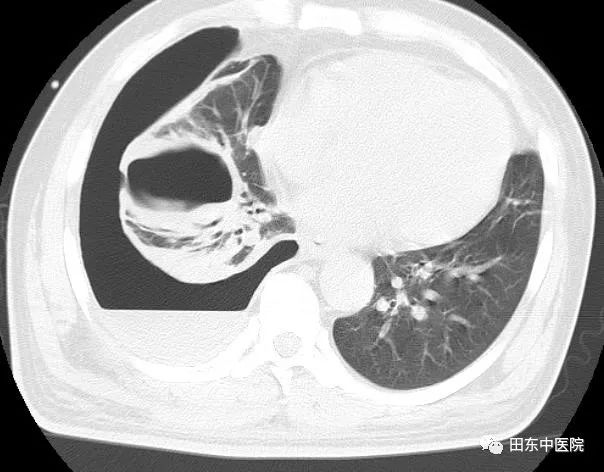

中午12点,一位体型肥胖病人走进了医生办公室,刚好交班结束的我接待了他,他自诉已胸痛了10天有余,先前因腰痛一直在院外治疗,没有好转遂到我院进行进一步的检查。详细了解完其病史后,我为其完善了体格检查:右侧胸胁部疼痛,呈持续性胀痛,有胸闷、呼吸困难,发热畏寒。查体见双侧呼吸运动不对称,两侧触觉语颤不对称,右肺叩诊浊音,右肺呼吸音消失。结合先前他在门诊做过的B超及后续补充的胸部CT结果,发现病人右侧胸腔有大量积液,为了解积液性质及缓解积液对肺脏的压迫,遂给病人行胸腔穿刺置管术,把胸腔里的积液引流出来。过程很顺利,术中抽出了约5000ml伴有腐臭气味的咖啡色脓液,术后病人的疼痛症状得到了极大的改善。

术前

术后